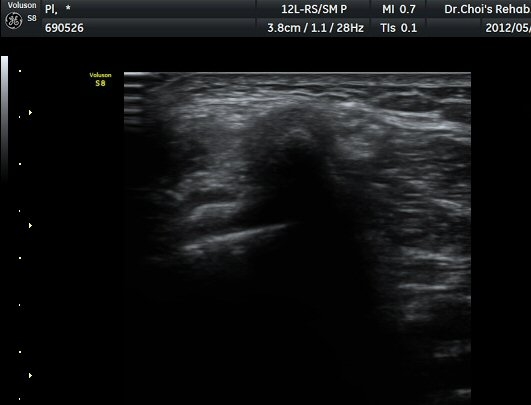

ŽÃËÁö¸¦ Á¶±Ý ´õ ¾Æ·¡·Î À̵¿ÇÏ´Ï »ÀÀÇ µÎ²²°¡ °¨¼ÒÇÏ´Â °ÍÀ» º¸°í ºñ°ñÀÇ ¸ñ ºÎÀ§¸¦ °üÂûÇϰí ÀÖÀ½À» ¾Ë ¼ö ÀÖ°í ÃѺñ°ñ ½Å°æÀº ºñ°ñ ¸ñ Ç¥Ãþ¿¡¼­ °üÂûµÈ´Ù(±×¸² 5).